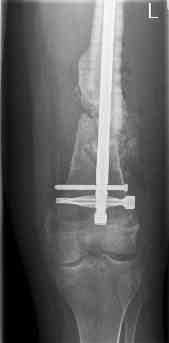

feb 07: retrograde nail + bone graft + BMP

may 07: dynamisation nail

sept 07: locking screw removal (max. dynamisation reached)

nov 07: persistant non-union distal femur; other fractures healed

uneventfully.